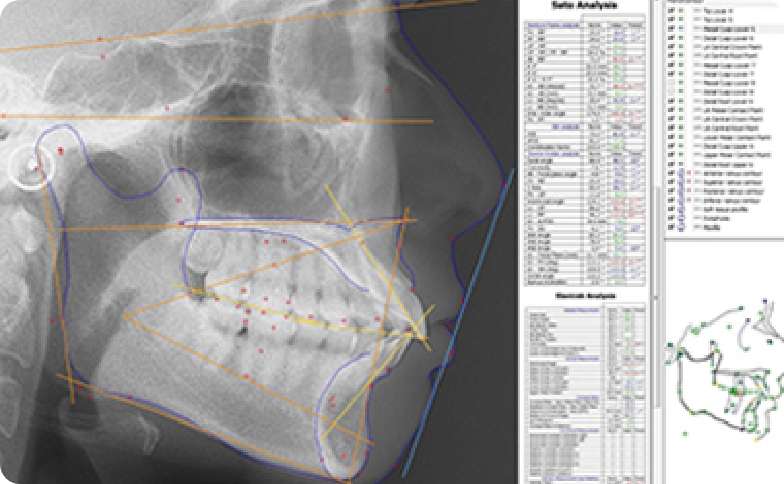

当院では、セファロ分析やCT撮影、デジタルスキャンなど多角的な検査を実施しています。歯の並びだけでなく、骨格や顔貌、咬み合わせの調和を数値で精密に分析。客観的なデータに基づき、将来の安定性まで見据えた、患者様に最も適した治療計画を誠実に立案いたします。

セファロ分析、CT撮影、デジタルスキャンなどの設備を導入し、骨格と歯の位置関係を数値化して診断を行います。ワイヤー矯正やインビザラインなど複数の治療法から、症例やご希望に合わせた方法をご提案します。見た目だけでなく、咬み合わせや安定性まで考慮した治療計画を立案しています。